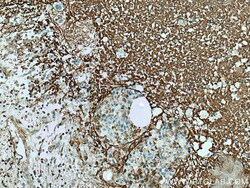

Immunohistochemistry

67604-1-IG IHC